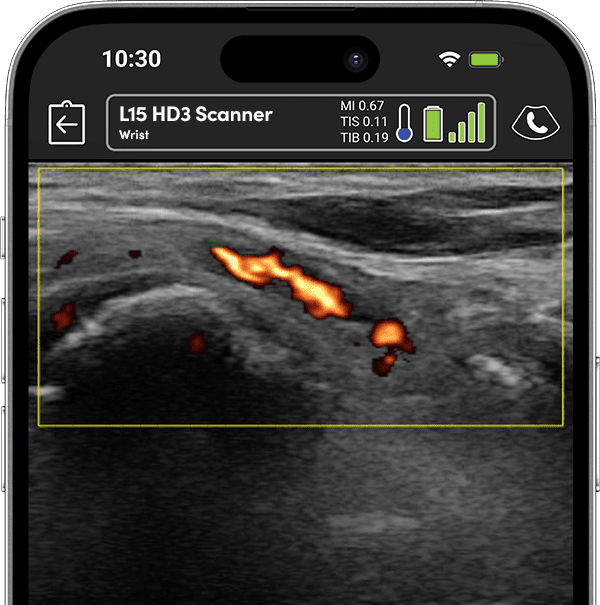

Precise Injections. Better Results.

Visualize targets in real time for precise nerve blocks and corticosteroid injections—reducing injectate volumes and boosting safety, confidence, and patient outcomes.

See Inflammation in Real Time.

Assess synovitis, enthesitis, and monitor treatment efficacy with high-resolution ultrasound, enabling precise, real-time joint and soft tissue evaluation, accurate needle guidance, and improved confidence in clinical decision-making.